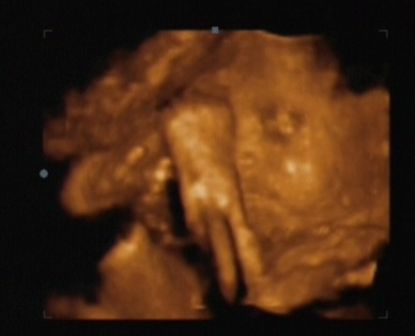

Egyébként Gergő baba engem jól megviccelt... tíz, majd később 5 perces fájásokat produkáltam rendszeres időközönként, elment a nyákcsap, úgyhogy elindultunk a kórházba. Bő kétujjnyi méhszájat mértek és befektettek... a gyerkőc mégis csak 3 hét múlva született meg.....